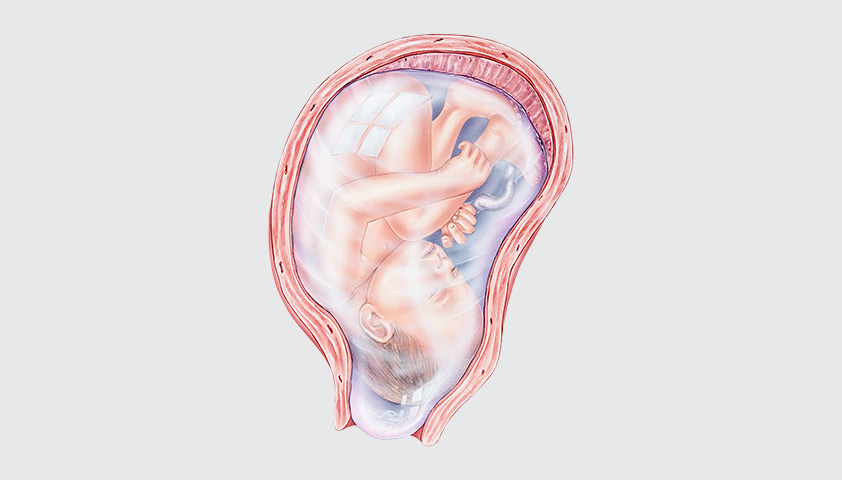

Многоводие при беременности: симптомы и лечение